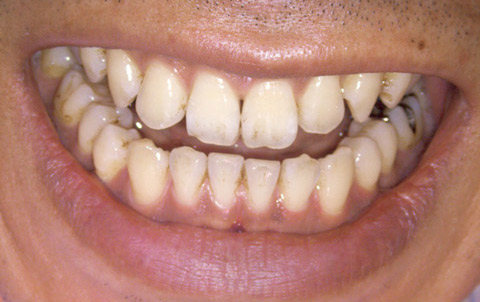

図1 術前。着色や歯石が見られる。

図11 術後の正面観